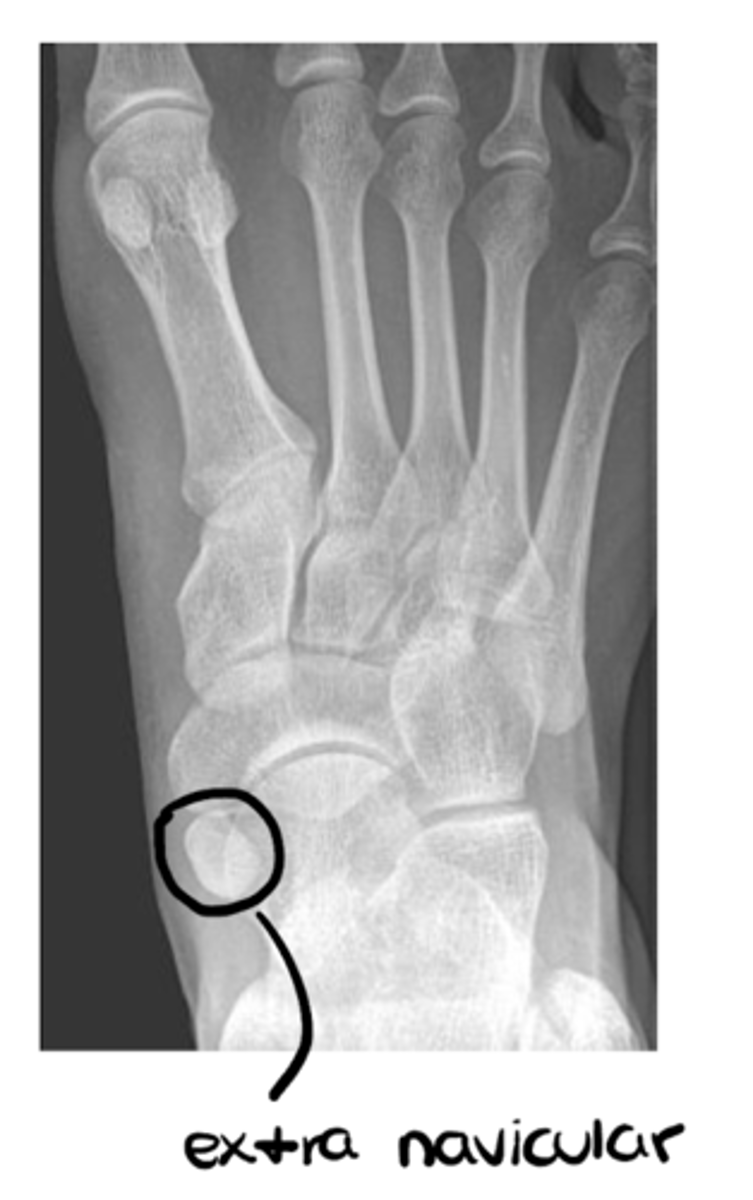

List the sub-components of (A) alignment: general architecture

- Aberrant size of bones

- Supernumerary bones (i.e., extra bones)

List the sub-components of (A) alignment: general contour

- Irregularities

- Cortical outline

- Spurs and osteophytes

- Fracture

Per the Ottawa Ankle Rules, when is an ankle x-ray series required?

Any pain in malleolar zone AND any of these findings:

- bone tenderness at 1 & 2 (i..e, posterior edge or tip of either malleolus)

- inability to bear weight both immediately and in ER

Any pain in midfoot zone AND any of these findings:

- bone tenderness at 3 & 4 (i.e., base of M5 or navicular)